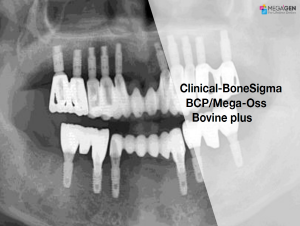

Clinical-BoneSigma BCP/Mega-Oss Bovine plus

Edentulous,Immediate loading,Aesthetic Zone,Bone regeneration,Mandibular Anterior,Mandibular Posterior,#33,#34,#36,#43,#44,#46,GBR,Mega-Oss Bovine plus,Clinical case

English

2019-10-01

PDF

448.15 Kb

Clinical cases

194